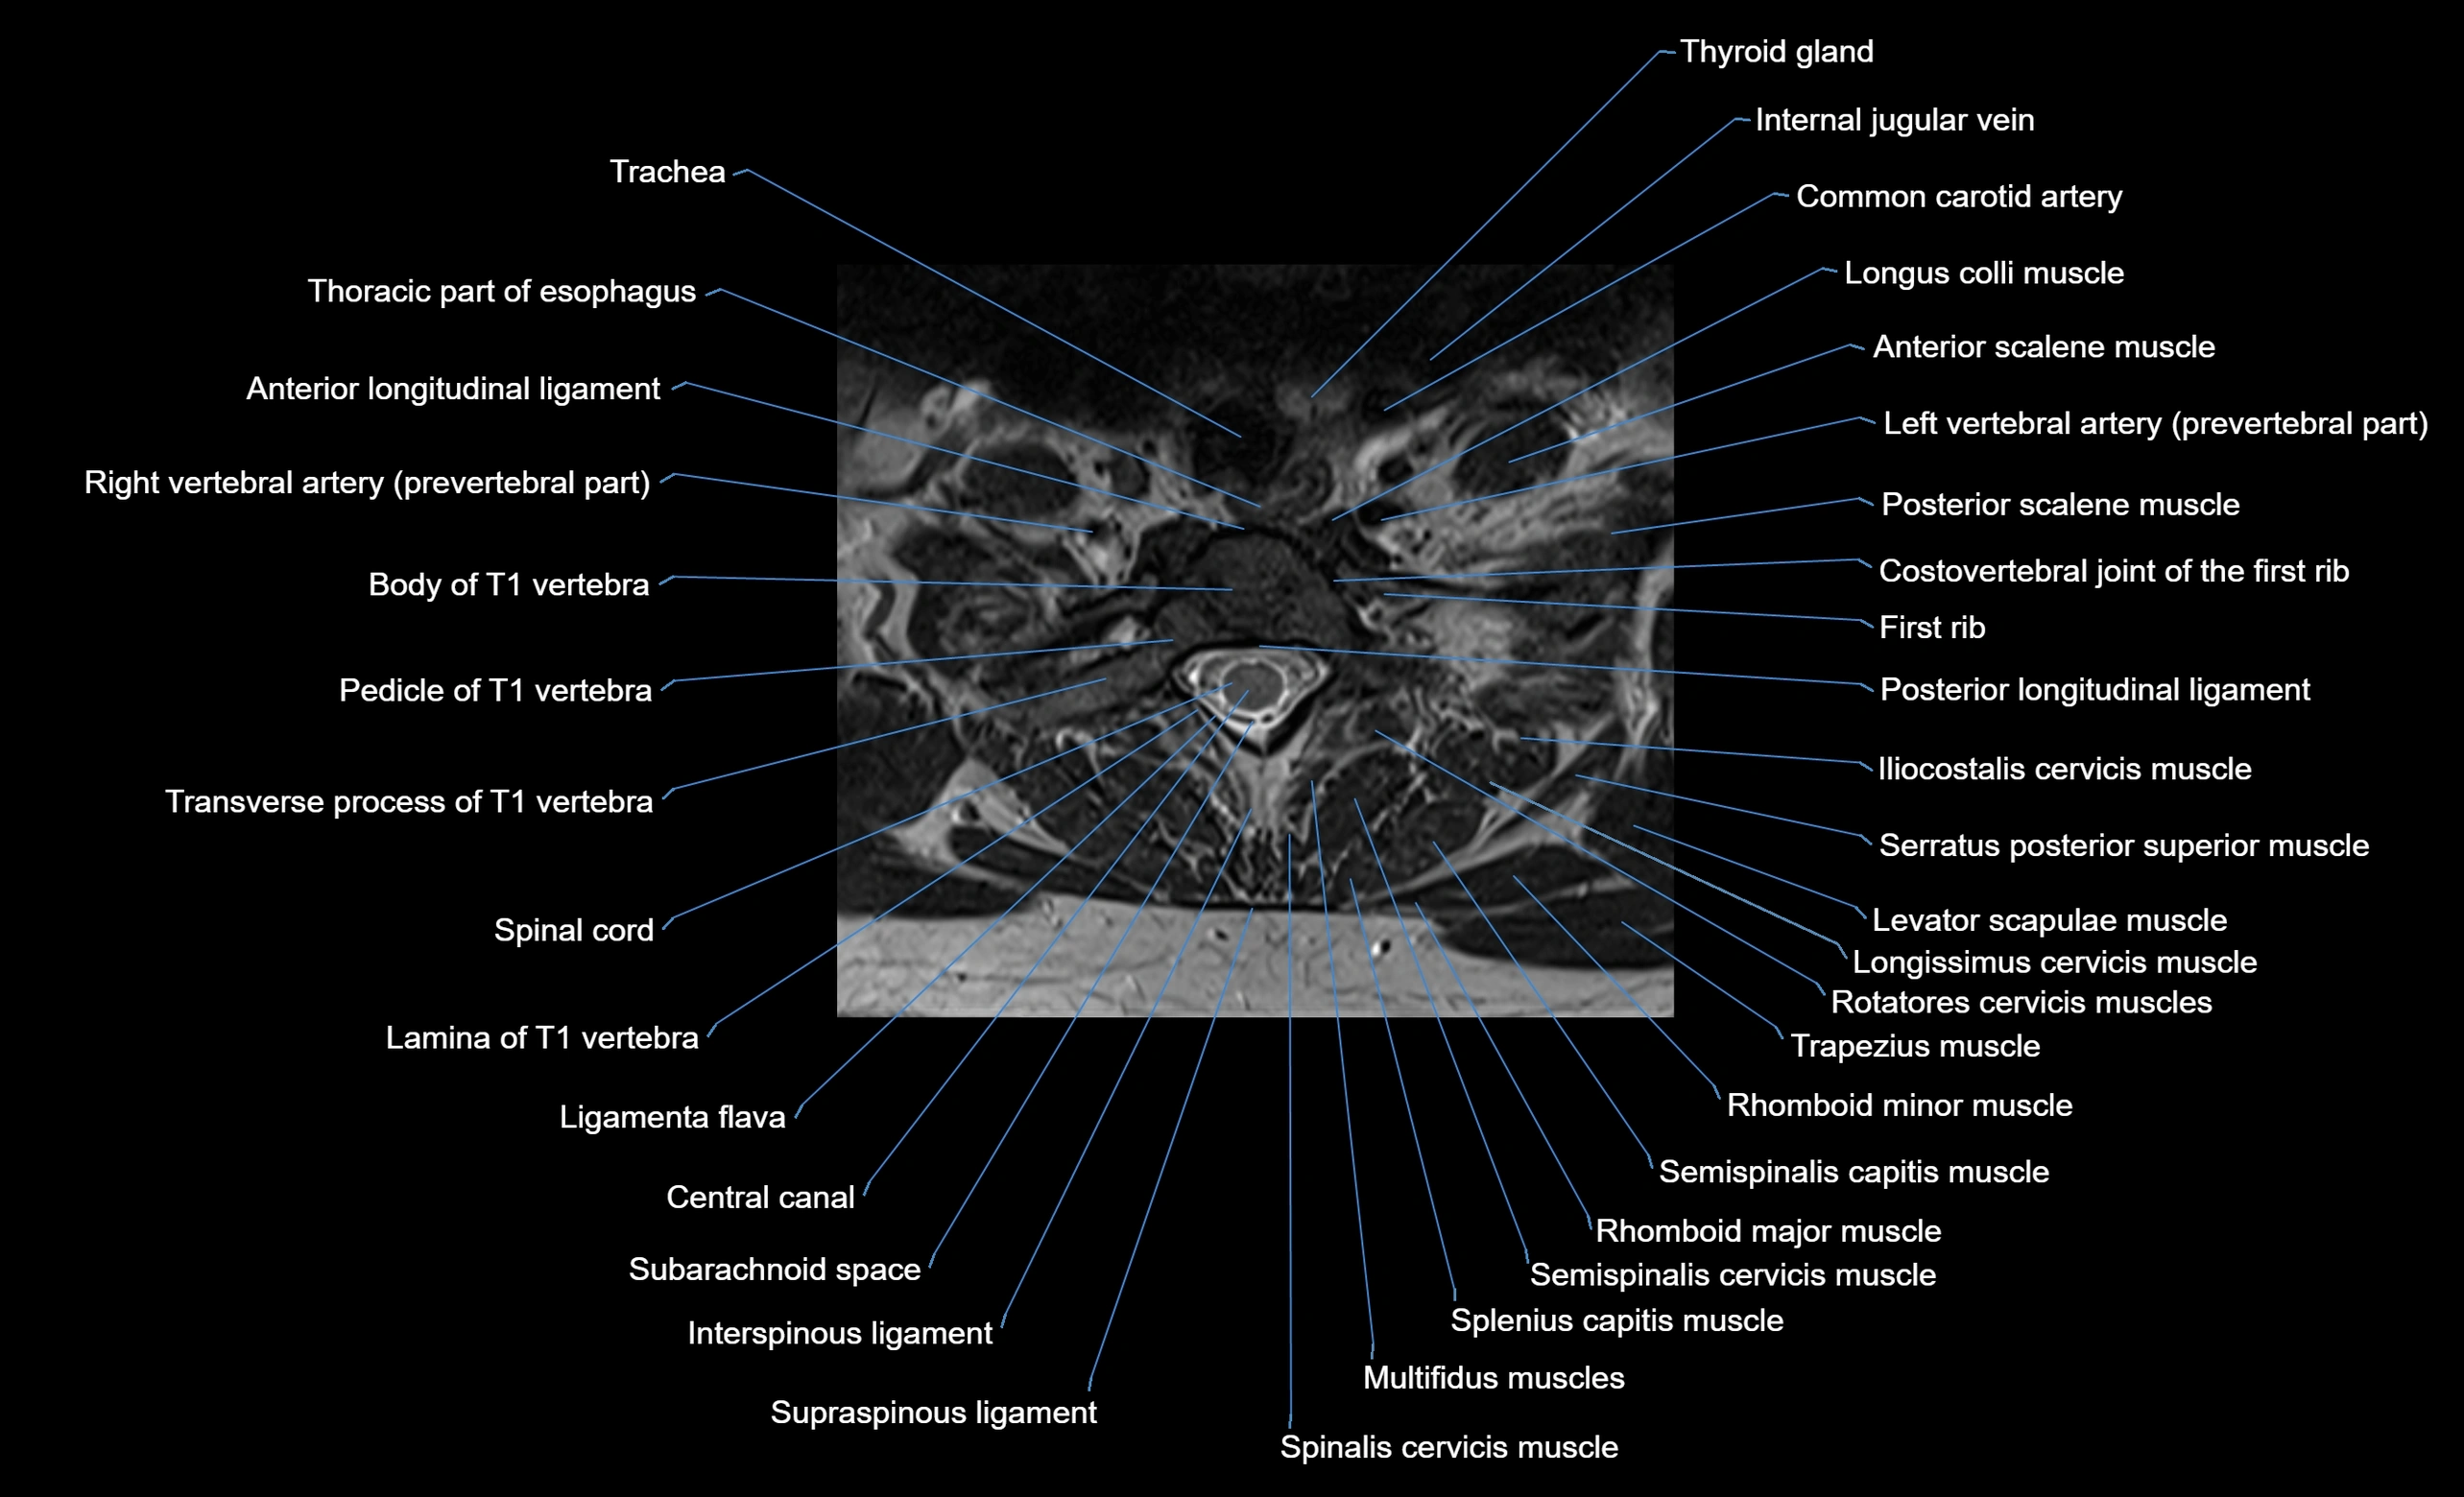

CT appearance

Pre-contrast CT:

• Annular epiphysis: Thin hyperdense bony ring at the vertebral endplate periphery

• Margins: Well-defined cortical outline

• Relationship: Clearly separated from central endplate in skeletally immature patients

• After fusion: Appears continuous with the vertebral body cortex

CT image

image